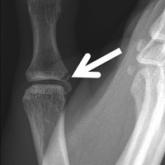

The ulnar collateral ligament (UCL) of the thumb metacarpophalangeal joint is a static stabilizer that may rupture from a hyperabduction injury....